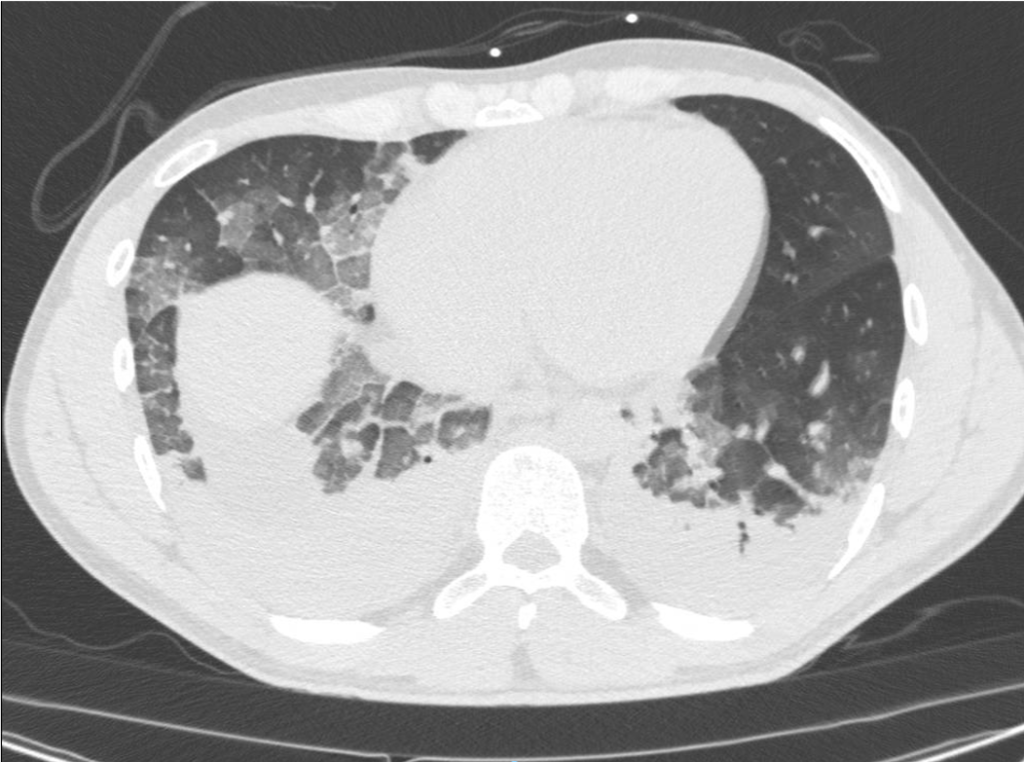

The patient tested positive for SARS-COV-2. On day 2 after admission the patient’s condition deteriorated, and he was transferred to the ICU. Another chest CT was performed. We show the ultrasound and CT images with corresponding legends (image 1-7 + video 1) and discuss the findings in relation to the diagnostic work-up of COVID-19 pneumonia.

On imaging, initial lesions are usually peripheral because SARS-COV-2 attacks the small distal airways. Several reports have described the findings in chest CT. Most commonly few, small, segmental ground glass opacities are seen peripherally and basal. These may deteriorate to become bilateral and multisegmental and finally consolidation and/or ARDS. Most common LUS signs are: vertical pleurogenic artifacts with varying degree of intensity (from few to confluent). These alternate with clear demarcation to A-lines in the same area, especially in the mid- and upper lung. Pleural thickening, sometimes marked, due to the presence of numerous, small subpleural consolidations. Lobar or translobar consolidations of large size and minimal pleural effusions. The LUS features match with the site and kind on CT.